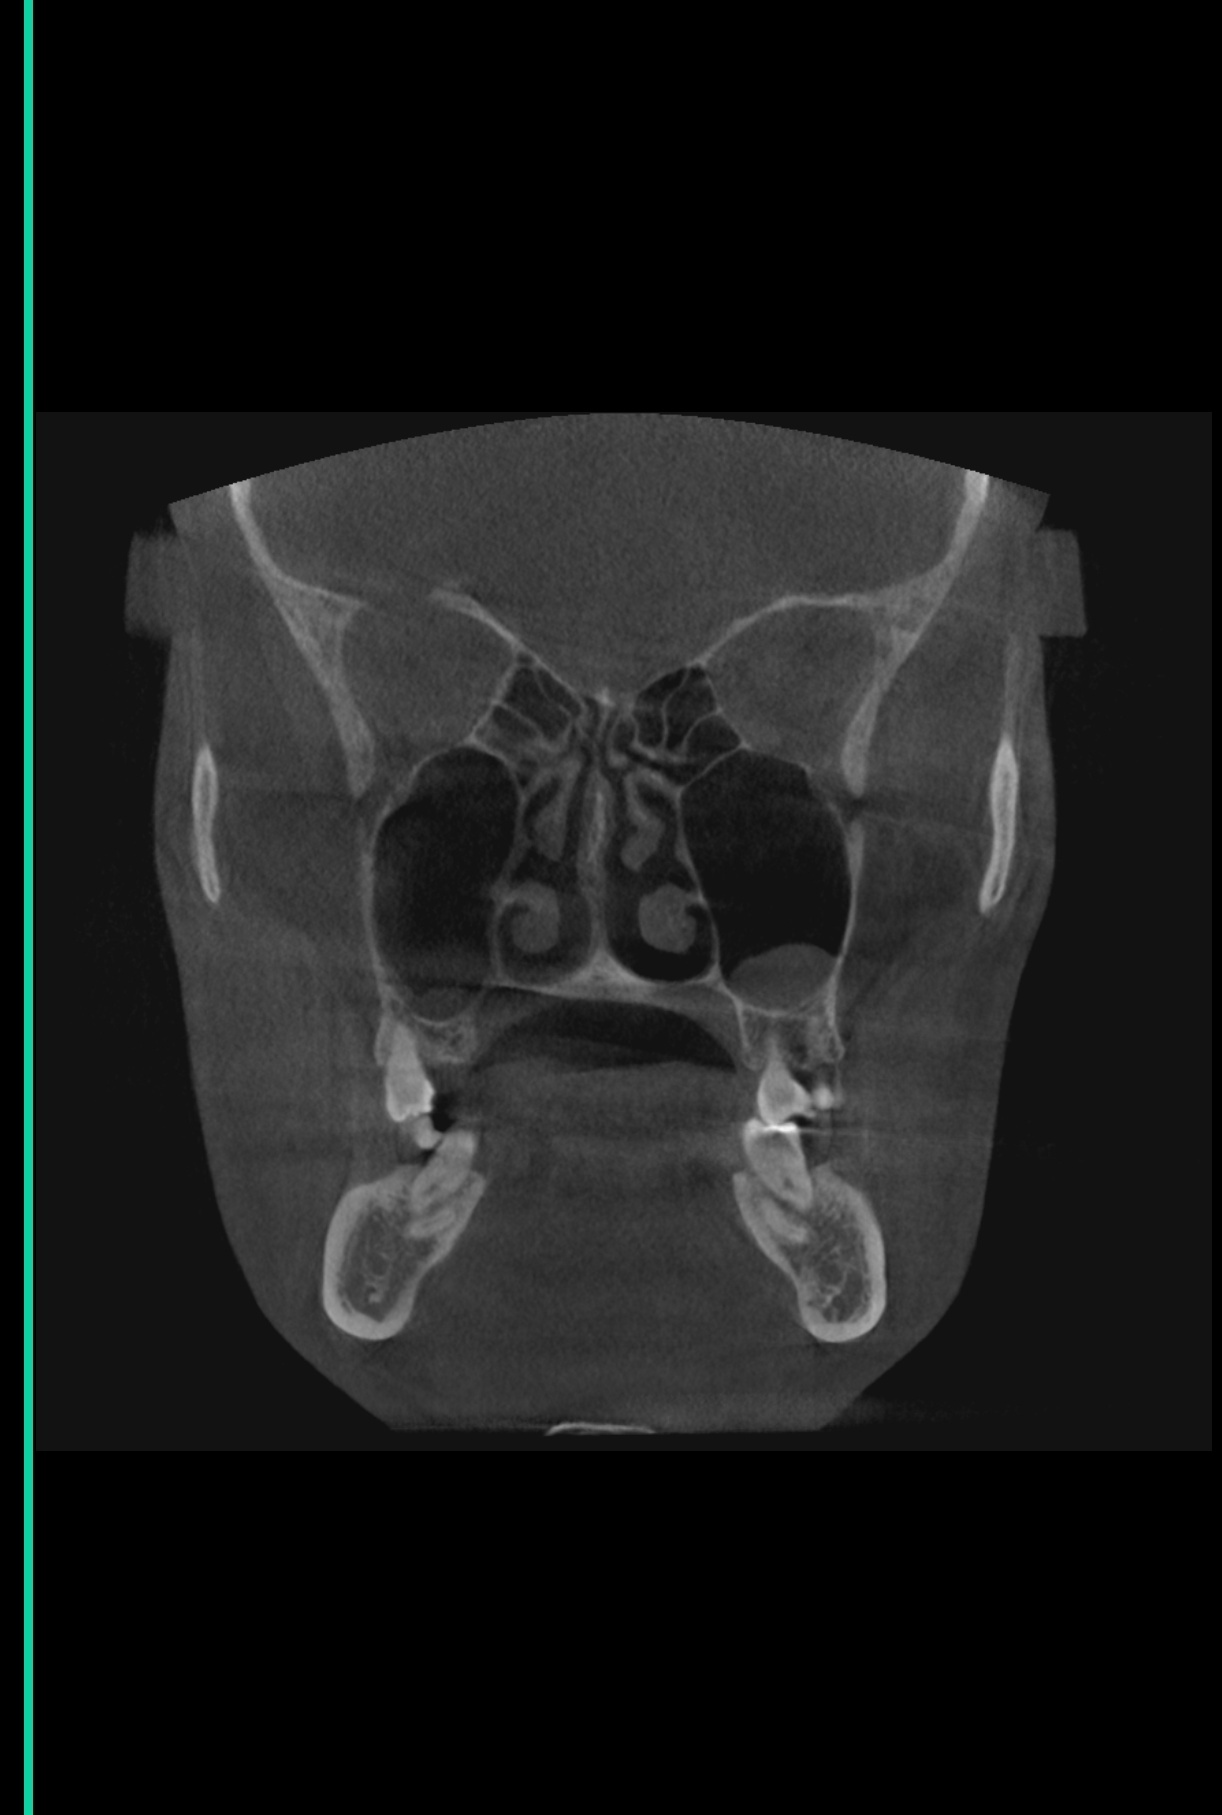

Тут же нужно выпрямлять носовые каналы или как это называется ? А то есть подозрение, что нудно будто бы всегда заложен и я чутка гундошу (когда слышу себя на записи)